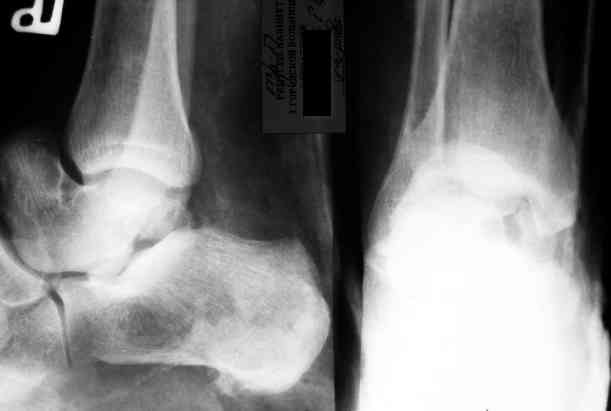

Уважаемый Александр! Как обещал представляю Р-граммы и операционные фото.

Последний снимок

Мнение по поводу тарана? АН есть?

> Мнение по поводу тарана? АН есть?

Типичная картина некроза.

На мой взгляд, у больного асептический некроз таранной кости, осложненный гнойным артритом голеностопного сустава (по снимку не понятно, что это - фистулография или простая рентгенограмма). Оптимален артродез голеностопного сустава, объем резекции таранной кости определится только интраоперационно. Большая проблема - метод фиксации. Работая, в основном, с пациентами пожилого и старческого возраста могу сказать, что ЧКОС они переносят плохо. Адекватный уход за аппаратом возможен только в условиях стационара. Возможность самостоятельной работы с аппаратом, например для ликвидации укорочения, крайне сомнительна. Кроме того, укорочение 3 см (до 5 см) у данной категории больных легче компенсировать ортопедической обувью. К сожалению и фиксирующие повязки (гипсовые и различные "касты")- не лучший вариант для пожилых людей (пролежни и флектены просто на "ровном месте"). В данном случае я бы применил простую "фиксирующею" компоновку аппарата Илизарова, с возможностью "отступления" к голеностопному брэйсу (тутору). Основная задача - максимальное восстановление самообслуживания больного и, по возможности, избежать "этапных" операций.

осложненный гнойным артритом голеностопного сустава (по снимку не понятно, что это - фистулография или простая рентгенограмма-

Ну гнойный артрит вряд ли, свищ-то есть, а всего остального (признаков артрита) нет. А снимок - обычная Р-грамма с артефактами.